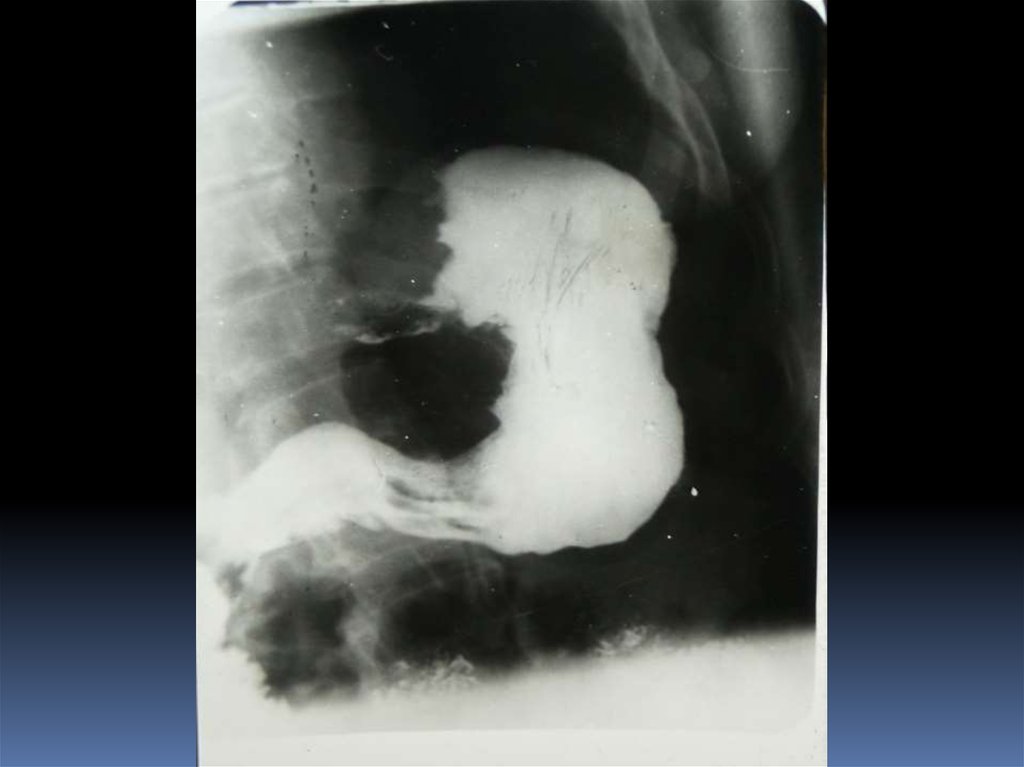

16. Рентгенодиагностика рака желудочно-кишечного тракта

Рентгенодиагностика

рака желудочнокишечного тракта

17. Классификация рака органов ЖКТ

1. Экзофитная форма:

2. Эндофитная форма:

узловая форма;

диффузноинфильтративная

форма;

полипоподобная

чашеподобная форма. инфильтративноязвенная.

3. СМЕШАННАЯ ФОРМА – 10-15%